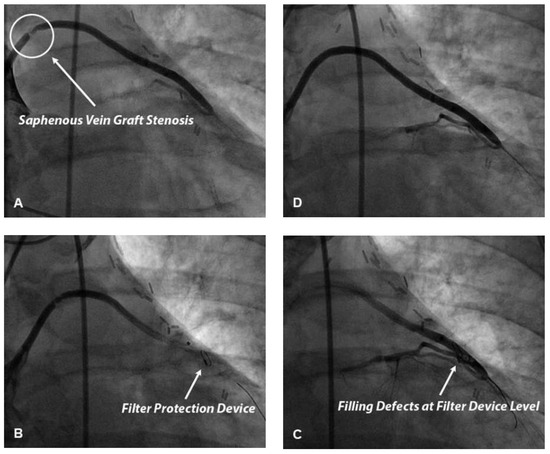

We present a case of false deployment of a self-expandable transcatheter aortic valve implantation (TAVI) prosthesis due to inadvertent and incorrect release of an eyelet in the crown of the valve resulting in a tilted valve. Hence the prosthesis had...